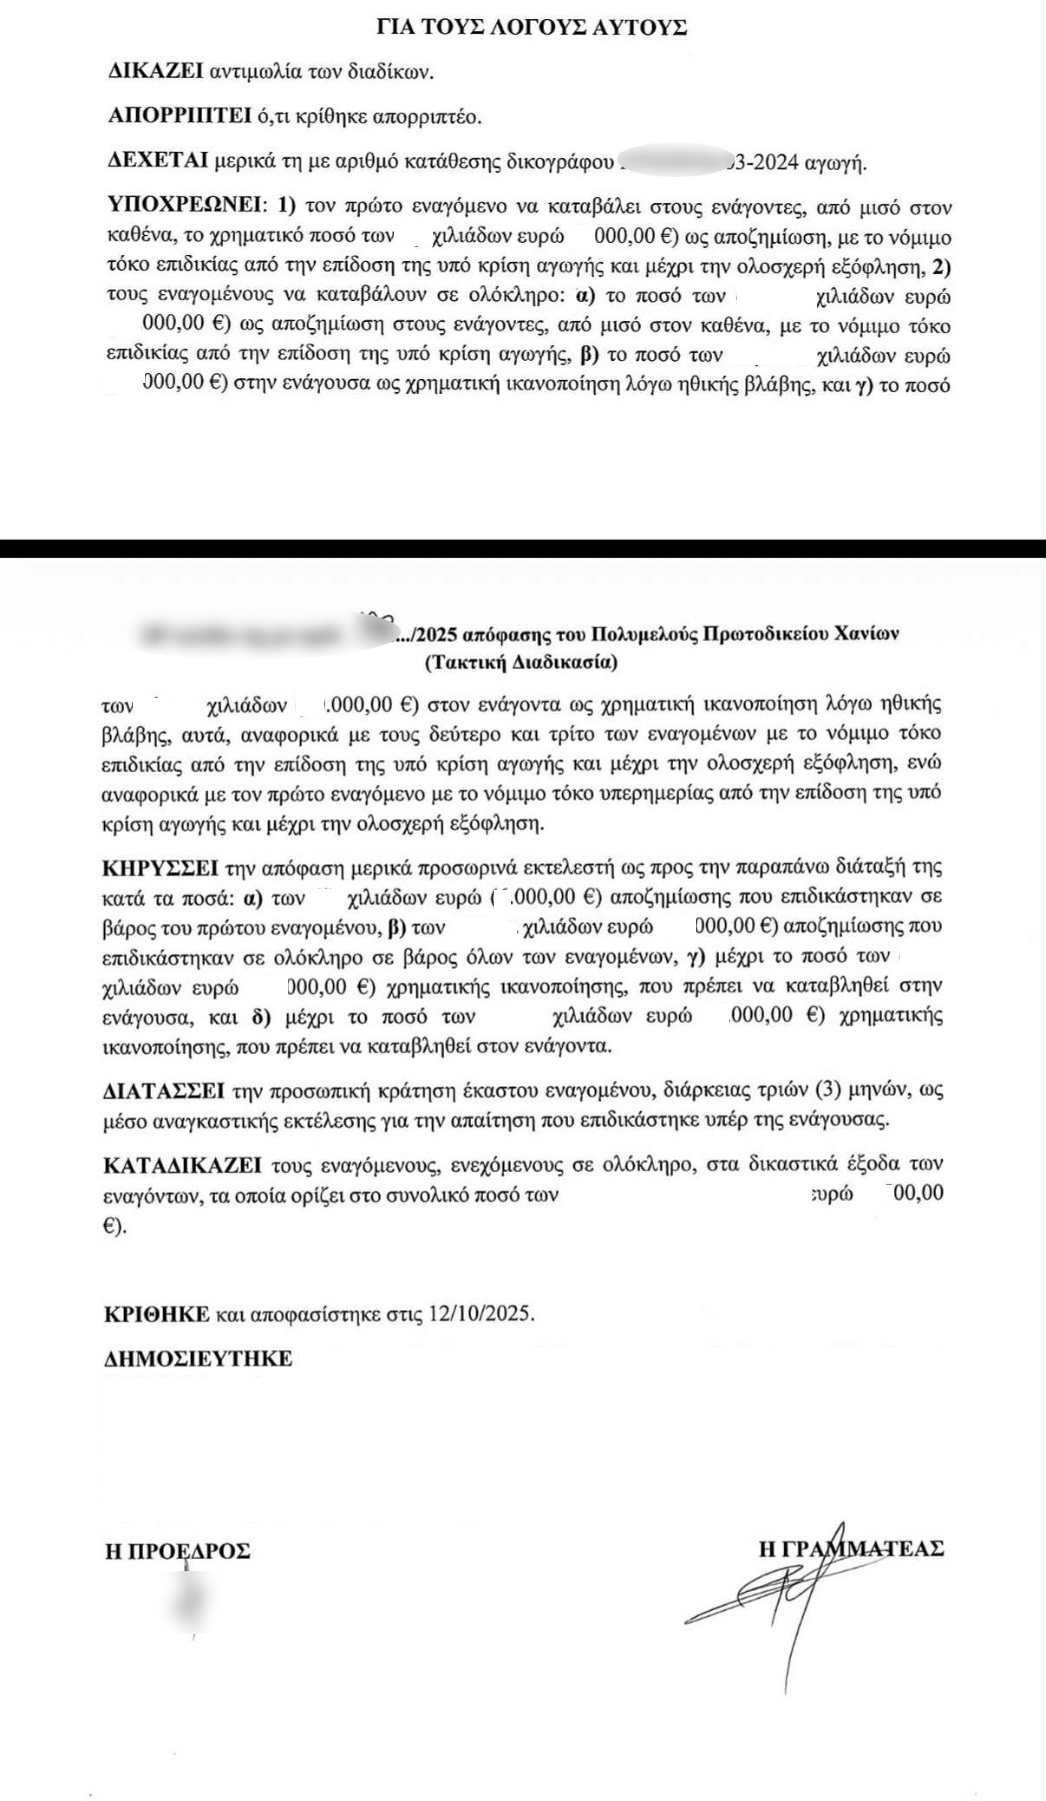

Το δικαστήριο αναγνώρισε ότι υπέστησαν τόσο σωματική όσο και ηθική βλάβη, και ανοίγοντας τον δρόμο της απόδοσης ευθυνών στους τρεις εμπλεκόμενους, τον 75χρονο γυναικολόγο – ιδιοκτήτη του κέντρου, τον 48χρονο εμβρυολόγο – διευθυντή και τον 60χρονο καθηγητή γυναικολογίας. Τους υποχρέωσε δε να αποδώσουν επιπλέον ποσό στο ζευγάρι ως χρηματική αποζημίωση για ηθική βλάβη.

Μόνο το έτος 2018, υποβλήθηκαν σε τέσσερις εμβρυομεταφορές λαμβάνοντας από τους υπεύθυνους ψευδή REPORT την ώρα που τα αληθή αρχεία τηρούνταν στα φύλλα εργαστηρίου IVF/ICSI LABOARATORY SHEET όπου οι Αρχές απέκτησαν πρόσβαση μετά την προφυλάκιση των δύο φερόμενων αρχηγών για την υπόθεση με τις παρένθετες, τον Αύγουστο του 2023.

Αν και η αστική διαδικασία είναι ανεξάρτητη με την ποινική, νομικοί κύκλοι εκτιμούν ότι η δικαίωση των πρώτων παθόντων, συνιστά ένα προηγούμενο που δίνει νέα τροπή στην υπόθεση που περιλαμβάνει τρεις πτυχές: Τη δικογραφία για τις παρένθετες μητέρες και το εμπόριο ωαρίων, τις εικονικές ιατρικές πράξεις και τα ενδεχόμενα οικονομικά εγκλήματα.

Ο Μάνος Μαλαξιανάκης και η Τώνια Φουράκη είναι ο πρώτοι άνρθωποι που αποζημιώνονται αφού το δικαστήριο έκριναν ότι έπεσαν θύματα μιας φρικτής απάτης, στην προσπάθειά τους να αποκτήσουν ένα παιδί.